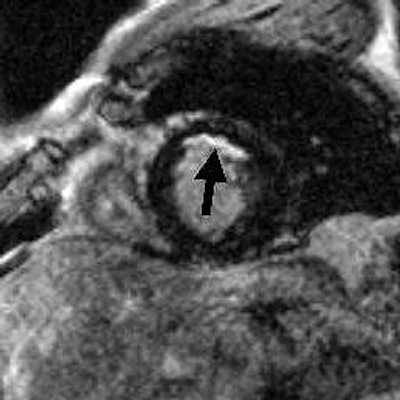

| Heart attack detected by cardiac MRI (in bright region indicated by arrow). Image courtesy of Robert Judd, Ph.D. |